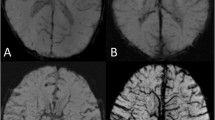

Model Application

The image segmentation algorithm model automatically identified and quantified DMV on the SWI MinIP images in 317 cases (Fig. 2a–c). The average number of identified DMV per case was 12.46 ± 5.58 (1–31), with a width of 0.73 ± 0.07 mm (0.49–0.93 mm) and a curvature of 1.10 ± 0.06 (range 1.03–1.57).